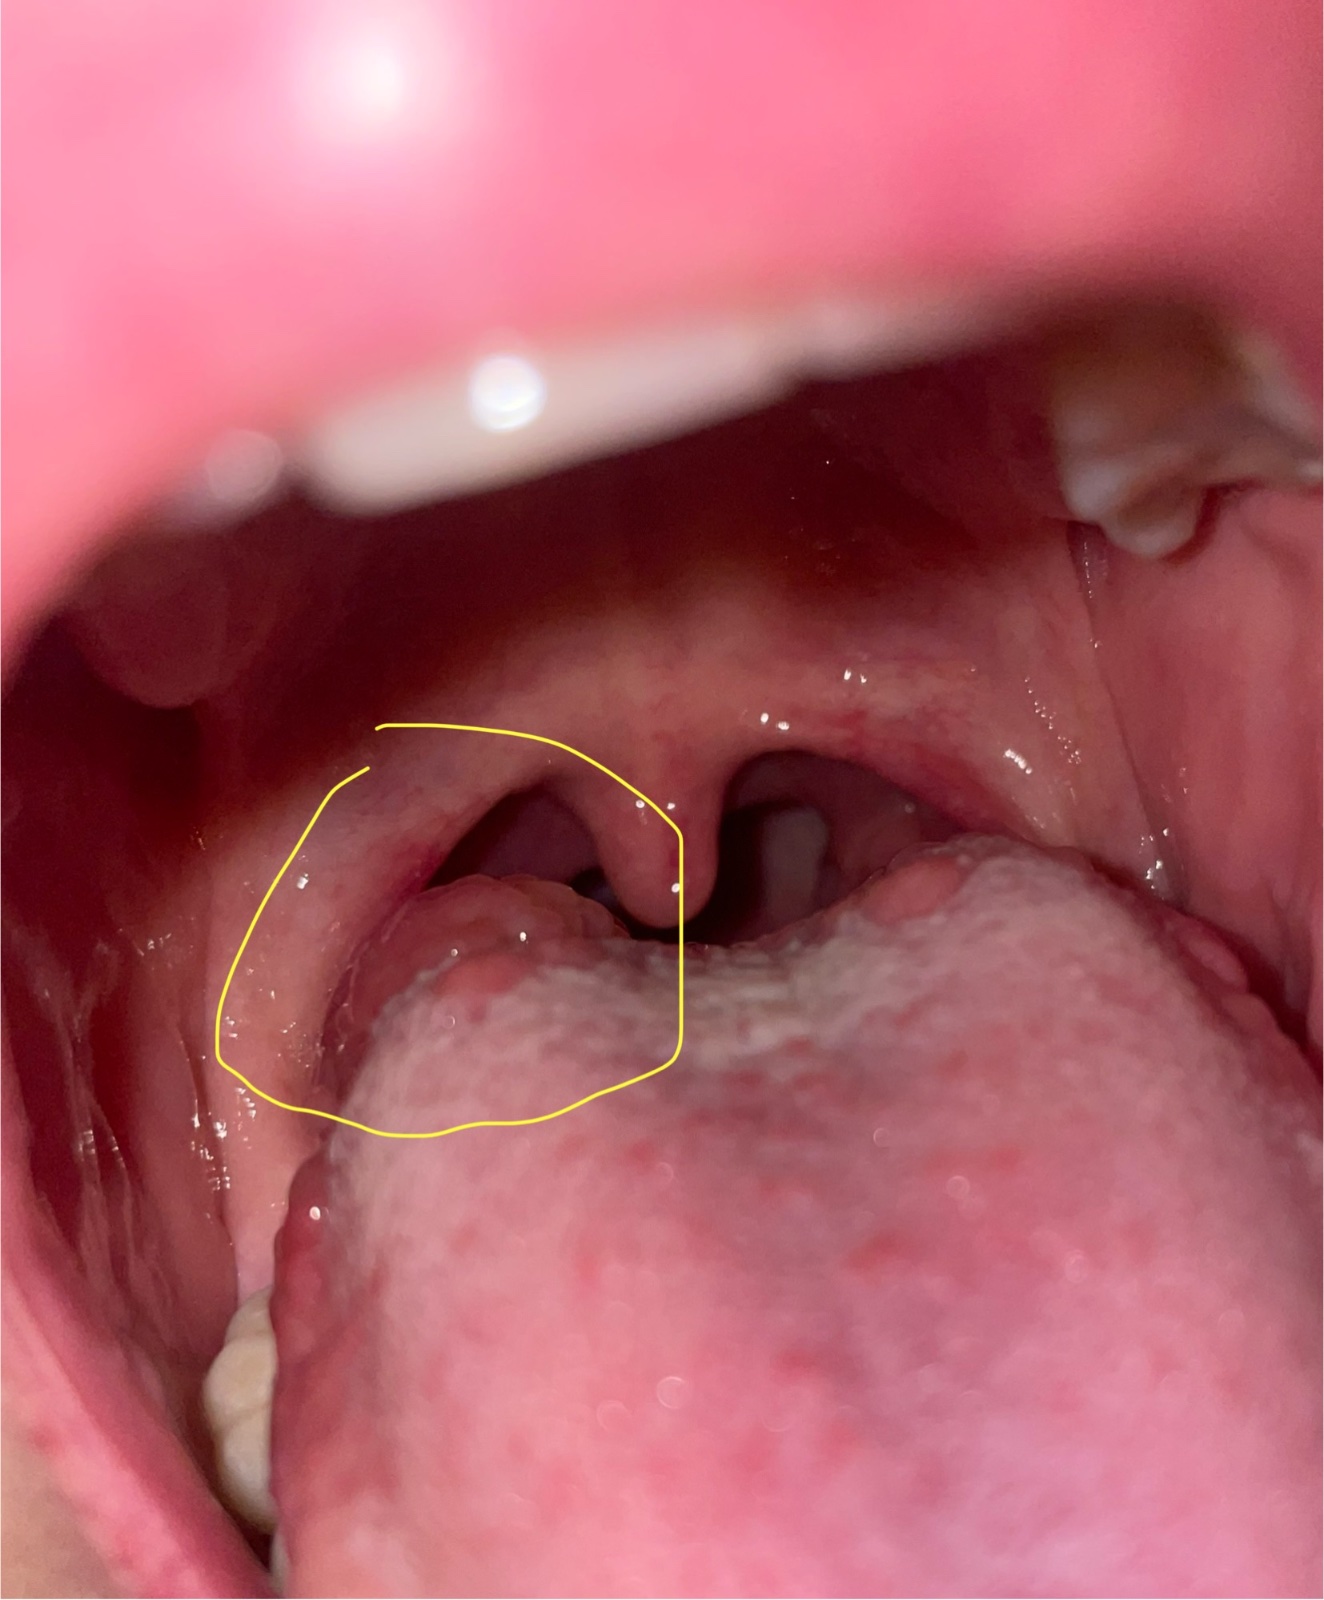

Ahoj, mám týden zvětšené chuťové papilly na konci jazyka. Na jednom místě je taková boule. Před měsícem jsem mela ve výtěru streptokoka a nasazen penicilin na 10dni. K lekari zajdu.. jen nemáte s tím někdo zkušenosti ? Strašně se bojim,ze jde o rakovinu nebo něco s lymfou. Dekuji za odpovědi

@belle_vie Ano to vim🙂 jen nechápu proč z nich mám takovou ,,boulicku, a na druhé straně jazyka ne.

@pribinak každý boulicku za poharkama nema..